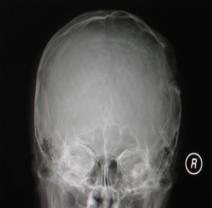

頭顱正側(cè)位片:可見右頂部顱骨缺損區(qū),局部軟組織隆起,類長圓形,缺損邊緣不規(guī)則、骨質(zhì)密度增高合并骨質(zhì)破壞密度減低,隆起如火山口狀(圖1)。

圖1:(1)正位相見右頂部骨質(zhì)缺損,局部軟組織隆起,邊緣不規(guī)則,骨質(zhì)密度增高合并骨質(zhì)破壞密度減低,隆起如火山口狀;(2)側(cè)位相見顱骨缺損區(qū),類似長圓形,缺損邊緣不規(guī)則